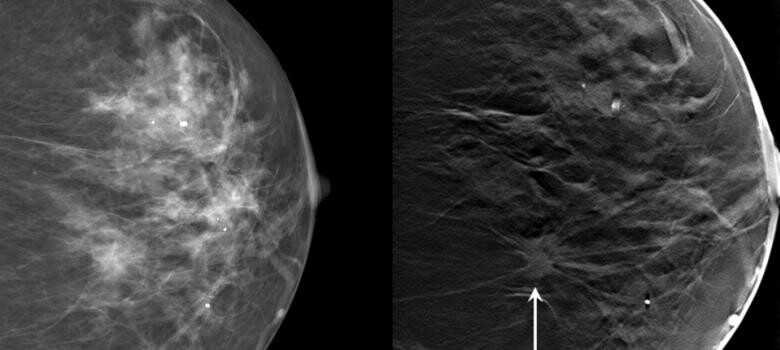

What Is 3D Mammography?

Digital breast tomosynthesis (3D mammography), available at all Duke Health mammography locations, is a new diagnostic tool for breast cancer detection. Jay Ba ...